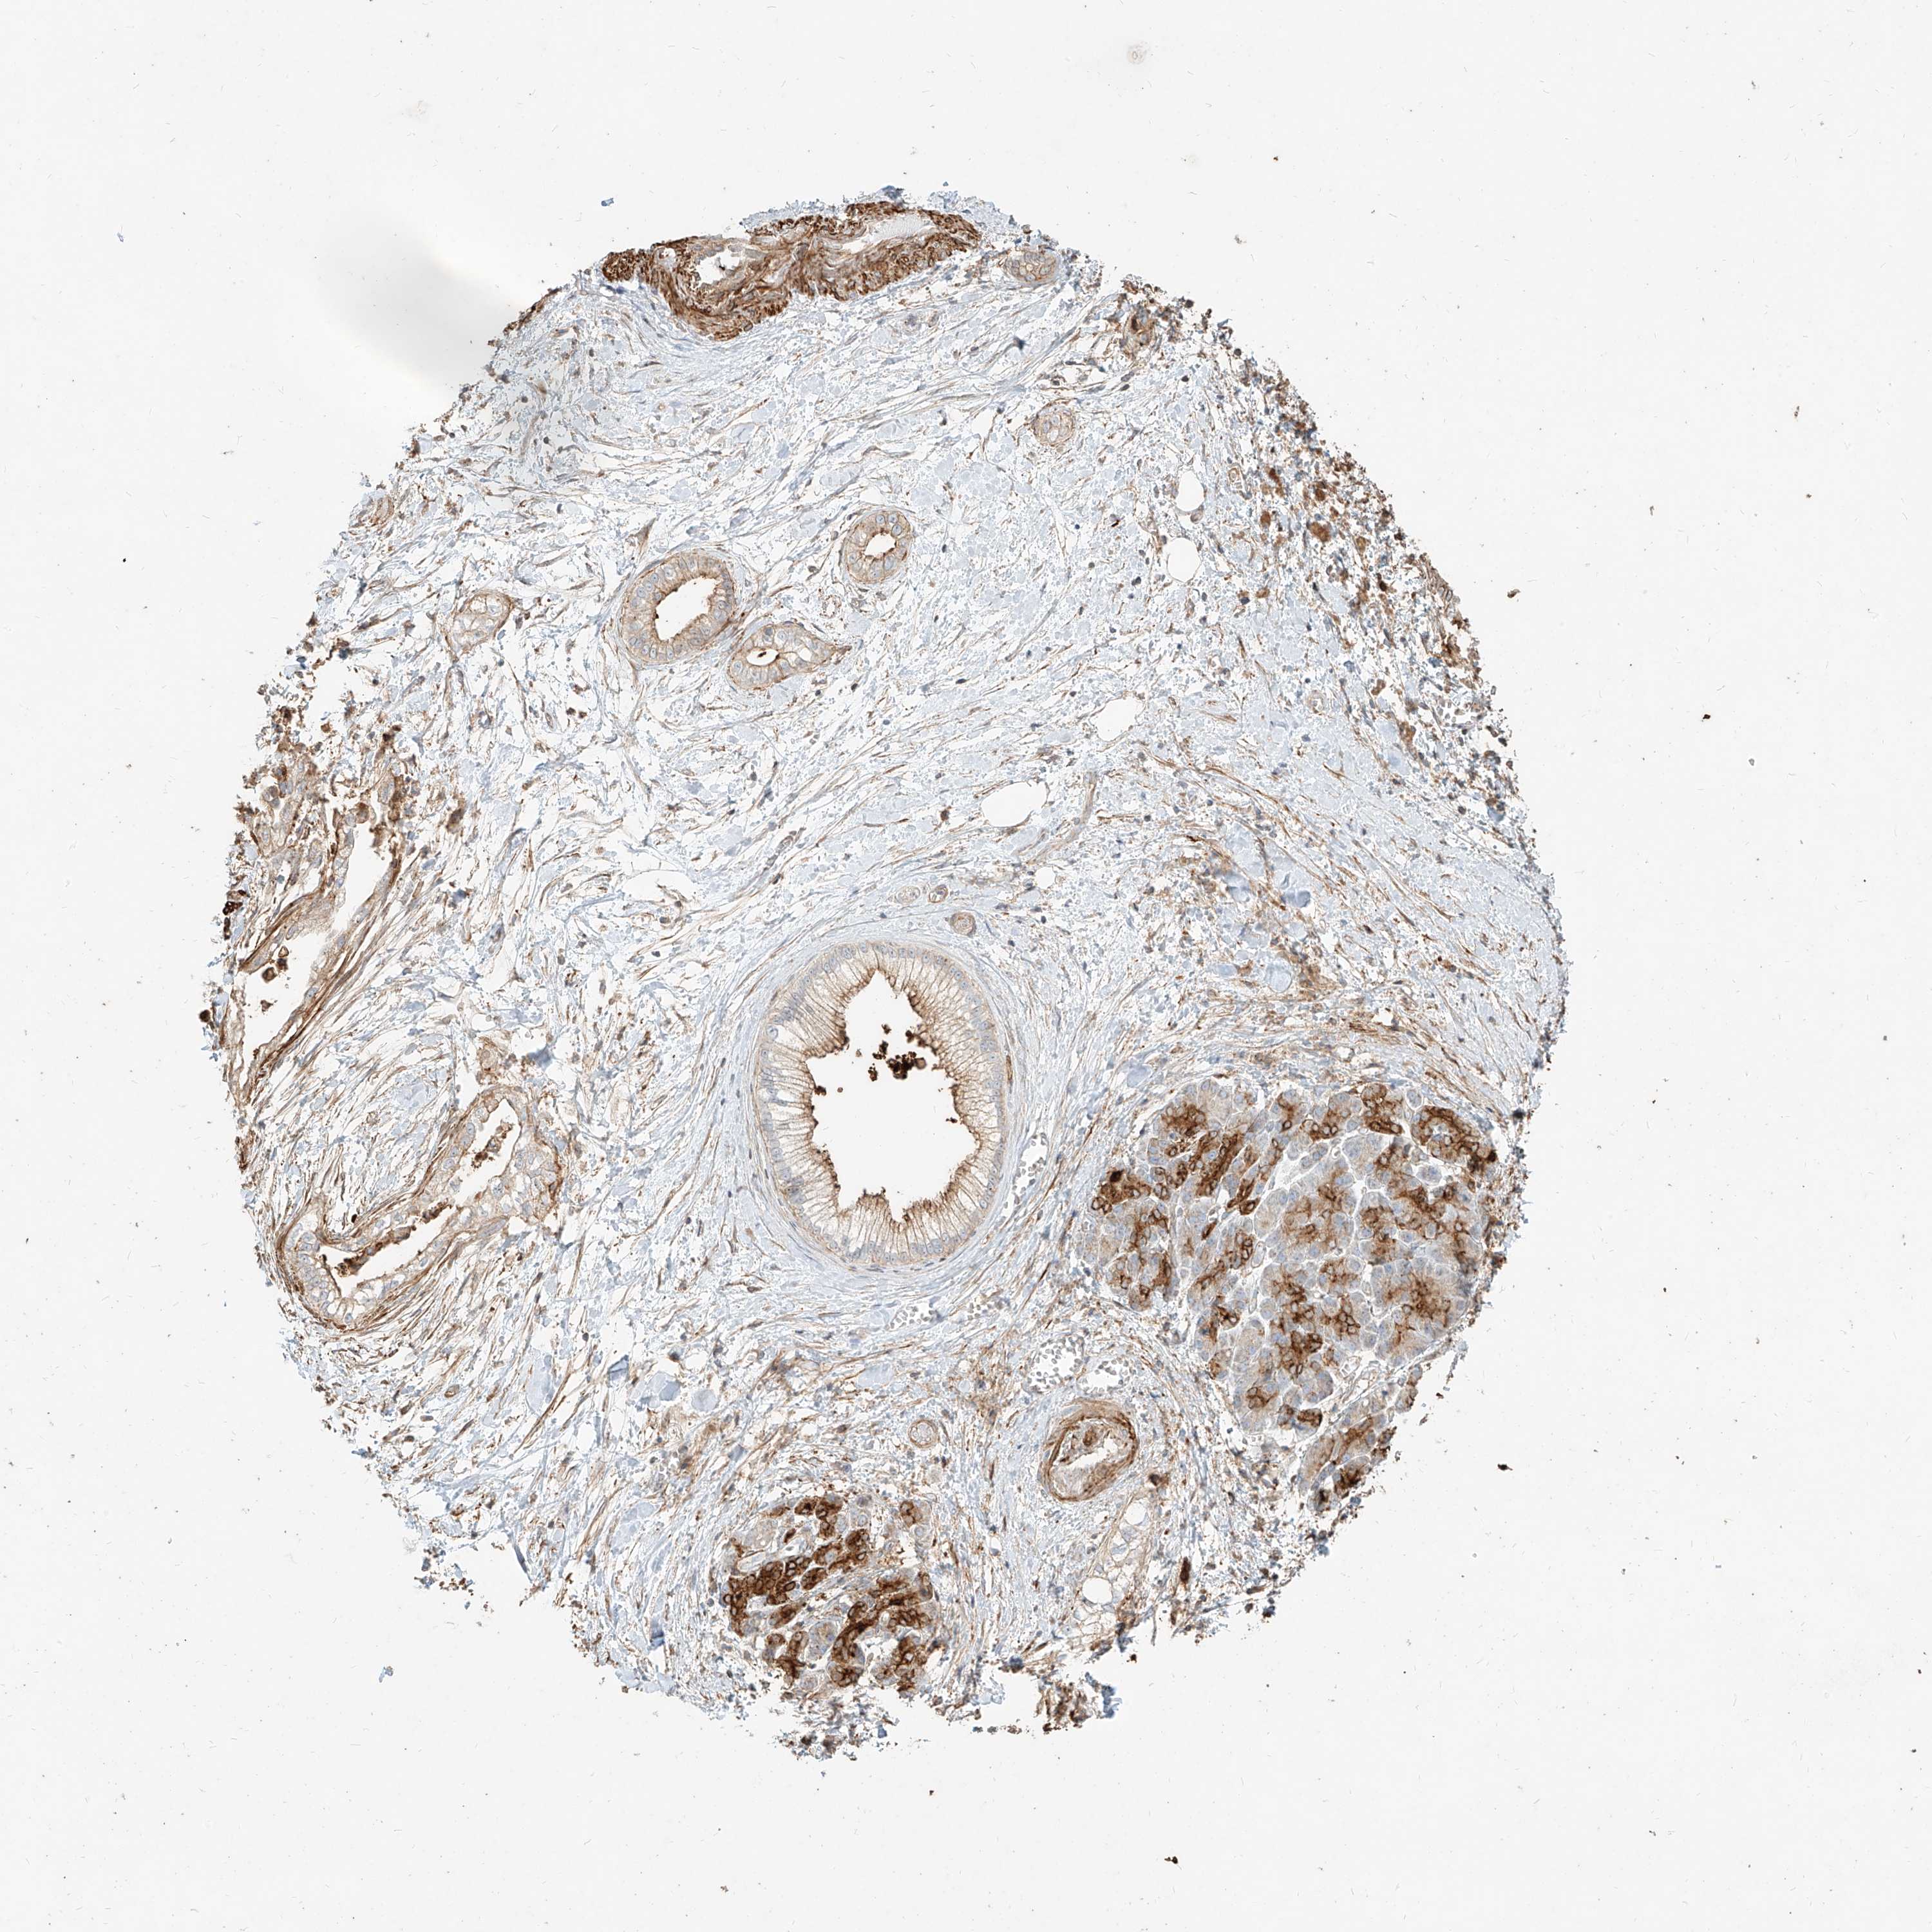

PANCREATIC CANCER - Protein expressioni

A mouse-over function shows sample information and annotation data. Click on an image to view it in a full screen mode. Samples can be filtered based on level of antibody staining by selecting one or several of the following categories: high, medium, low and not detected. The assay and annotation is described here.

Note that samples used for immunohistochemistry by the Human Protein Atlas do not correspond to samples in the TCGA dataset.

Antibody stainingi

Antibody staining in the annotated cell types in the current human tissue is reported as not detected, low, medium, or high, based on conventional immunohistochemistry profiling in selected tissues. This score is based on the combination of the staining intensity and fraction of stained cells.

Each image is clickable and will lead to virtual microscopy that enables deeper exploration of all samples and also displays staining intensity scores, fraction scores and subcellular localization as well as patient and tissue information for each sample.

Antibody HPA031550

Antibody HPA031551

Antibody HPA031552

Staining

High

Medium

Low

Not detected

Intensity

Strong

Moderate

Weak

Negative

Quantity

>75%

75%-25%

<25%

None

Location

Nuclear

Cytoplasmic/membranous

Cytoplasmic/membranous,nuclear

Adenocarcinoma, NOS